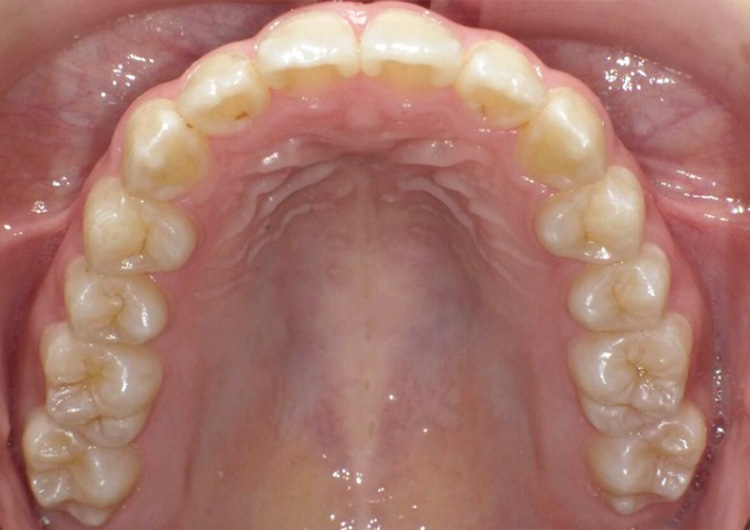

歯並びを治したい

| 主訴 | 歯並びを治したい |

| 治療内容 | インビザライン(マウスピース矯正)にて矯正治療を行なった。 |

| 主訴 | 歯並びを治したい |

| 治療内容 | インビザライン(マウスピース矯正)にて矯正治療を行なった。 |